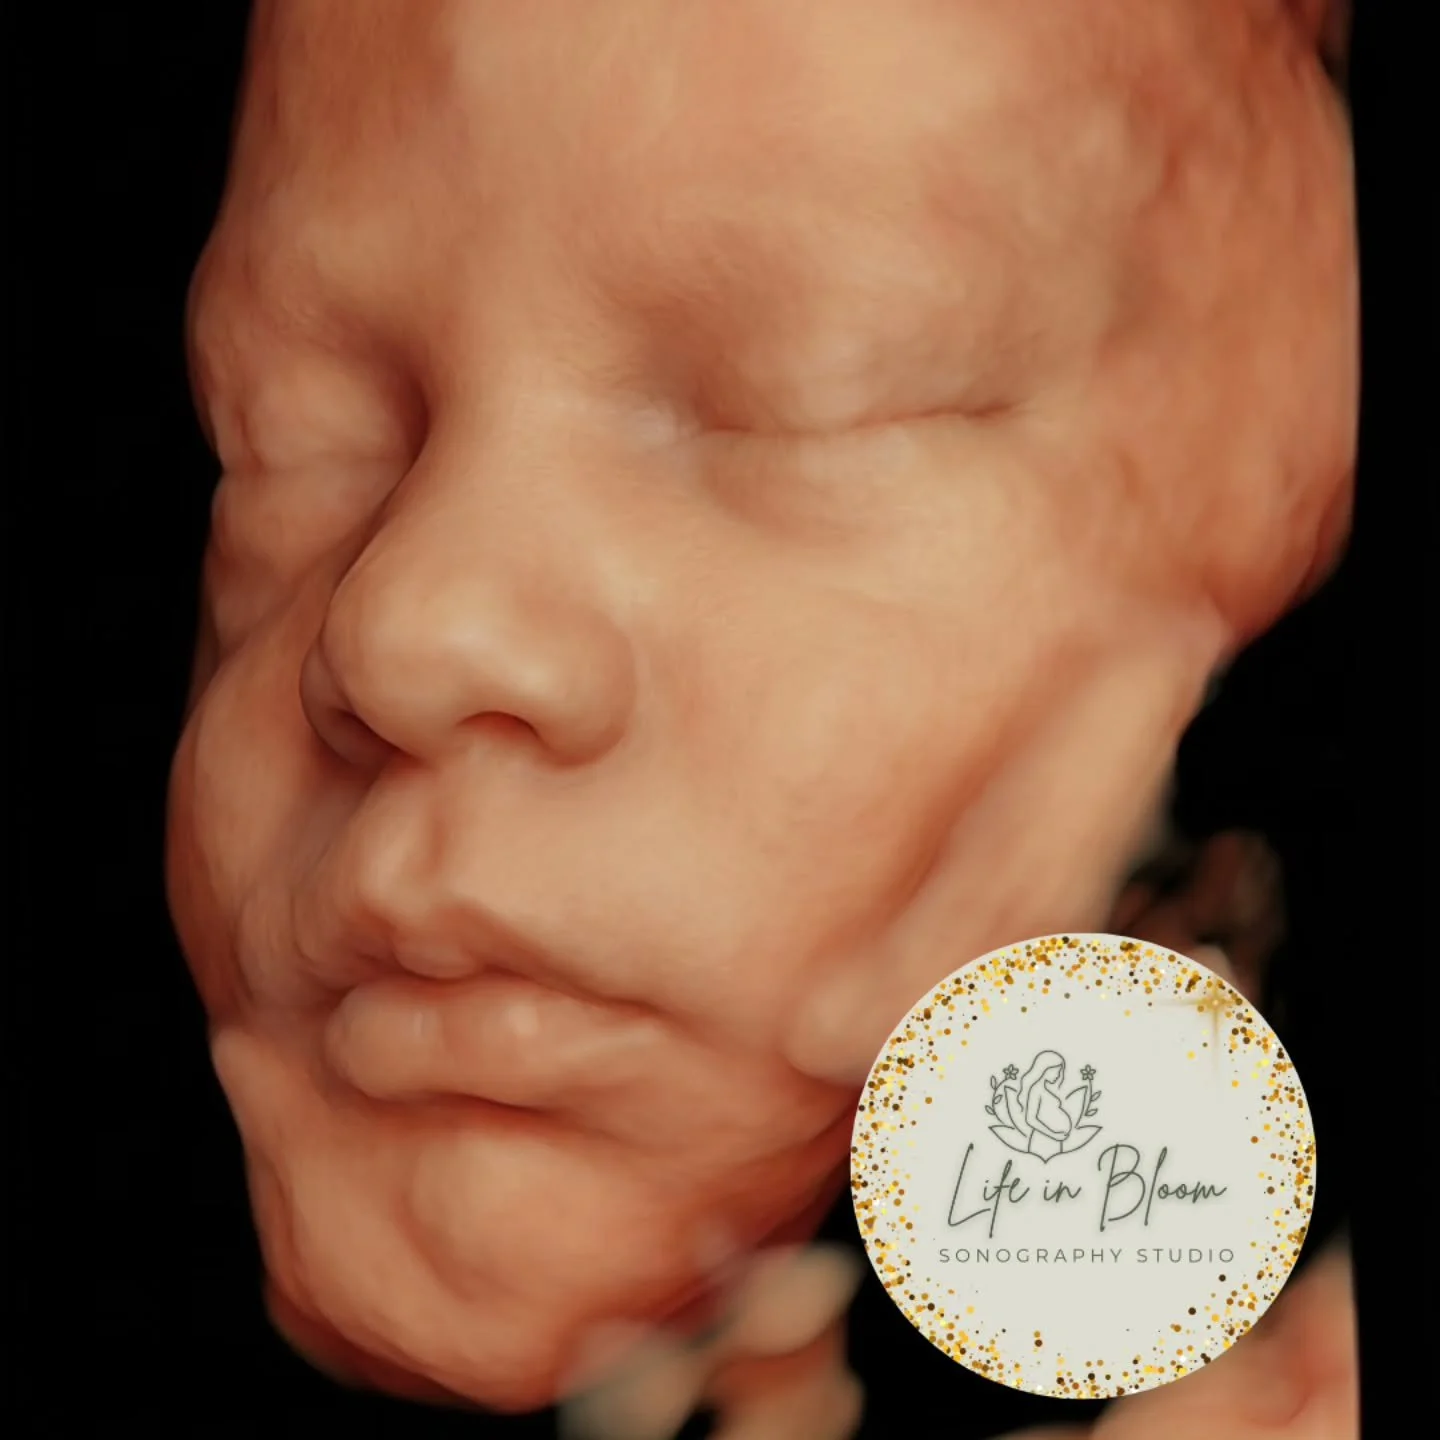

Our state of the art technology allows us to see your baby in a whole different way! With HD Live imaging, we can watch your baby wiggle, smile and yawn all in real time!

With over 14 years of experience as a Registered Sonographer, Life in Bloom Sonography Studio was created with one clear intention: to offer families more than an ultrasound — an experience rooted in care, expertise, and connection.

Every session is guided by advanced training, a deep understanding of fetal imaging, and a genuine passion for creating meaningful moments for growing families. From the first scan to the final keepsake, each detail is handled with precision, patience, and heart.

Life in Bloom Sonography Studio is proudly accredited by the Better Business Bureau and has been recognized as a Best of 2025 Pregnancy Care Center by Business Rate, reflecting a commitment to excellence, professionalism, and trust within our community.